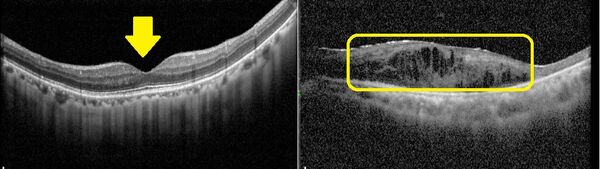

▲正常黃斑部的結構層次分明,中央呈現凹陷(圖左箭頭處),而黃斑部病變會因水腫造成結構模糊、隆起(圖右框線處)。

黃斑部病變分為乾性與濕性兩類,賴旗俊解釋,乾性病變約佔8成,病程進展慢,目前無特效藥,只能靠改善生活習慣延緩惡化,如配戴太陽眼鏡防止強光照射、戒菸、控制三高、補充抗氧化營養素等;濕性病變惡化速度快,主要是由新生血管異常增生造成出血與水腫,需透過眼內玻璃體注射抗血管新生藥物治療。